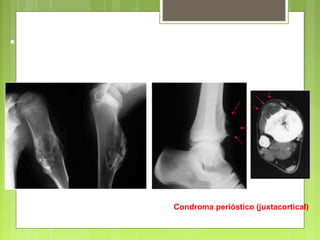

Condroma perióstico (juxtacortical)

• Invasión de partes blandas